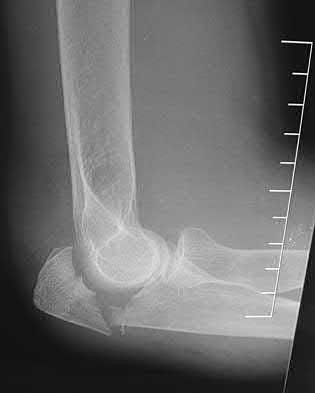

1012) A 54-year-old woman sustains the injury seen in Figures 71a and 71b. The injury involves her nondominant extremity. What should the patient be told regarding her expected outcome?

Corrent answer: 3

This is a Bado type 2 (posterior) Monteggia lesion, which is associated with higher rates of complications than other types of Monteggia lesions. The injury is associated with indirect high-energy trauma and less often pathologic causes. Of the four types of Monteggia lesions, the type 2 or posterior type is associated with the worst prognosis. These injuries are best treated surgically with dorsal plating of the ulna and reduction with fixation or arthroplasty of the radial head. The major complications seen with this injury pattern are nonunion and plate failure. Almost all patients have some loss of elbow range of motion. Satisfactory results based on functional scores for this injury are not universal. Neurologic injury and ulnohumeral instability are unusual with this type of injury. Full functional recovery is not expected with nonsurgical management.